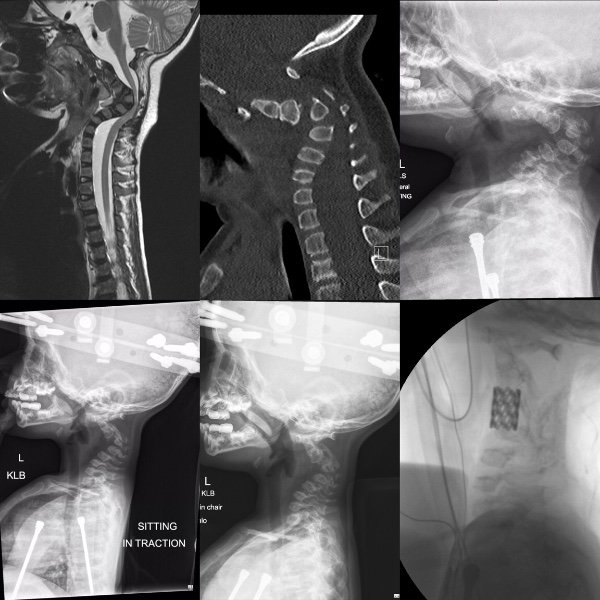

Diagnosticaram a bebê com osteogênese imperfeita, uma doença conhecida comumente como ossos de vidro.

Mas os jovens pais não queriam perder sua primogênita e decidiram trazê-la ao mundo. Deram a ela o nome de Zoe. Ao nascer, os médicos a diagnosticaram com osteogênese imperfeita tipo III, não a tipo II, que era o que imaginavam anteriormente.

Essa era uma boa notícia, já que é possível se viver com a tipo III, mesmo que ela ainda seja muito séria. Depois de uma semana no hospital, eles puderam levar Zoe para casa.